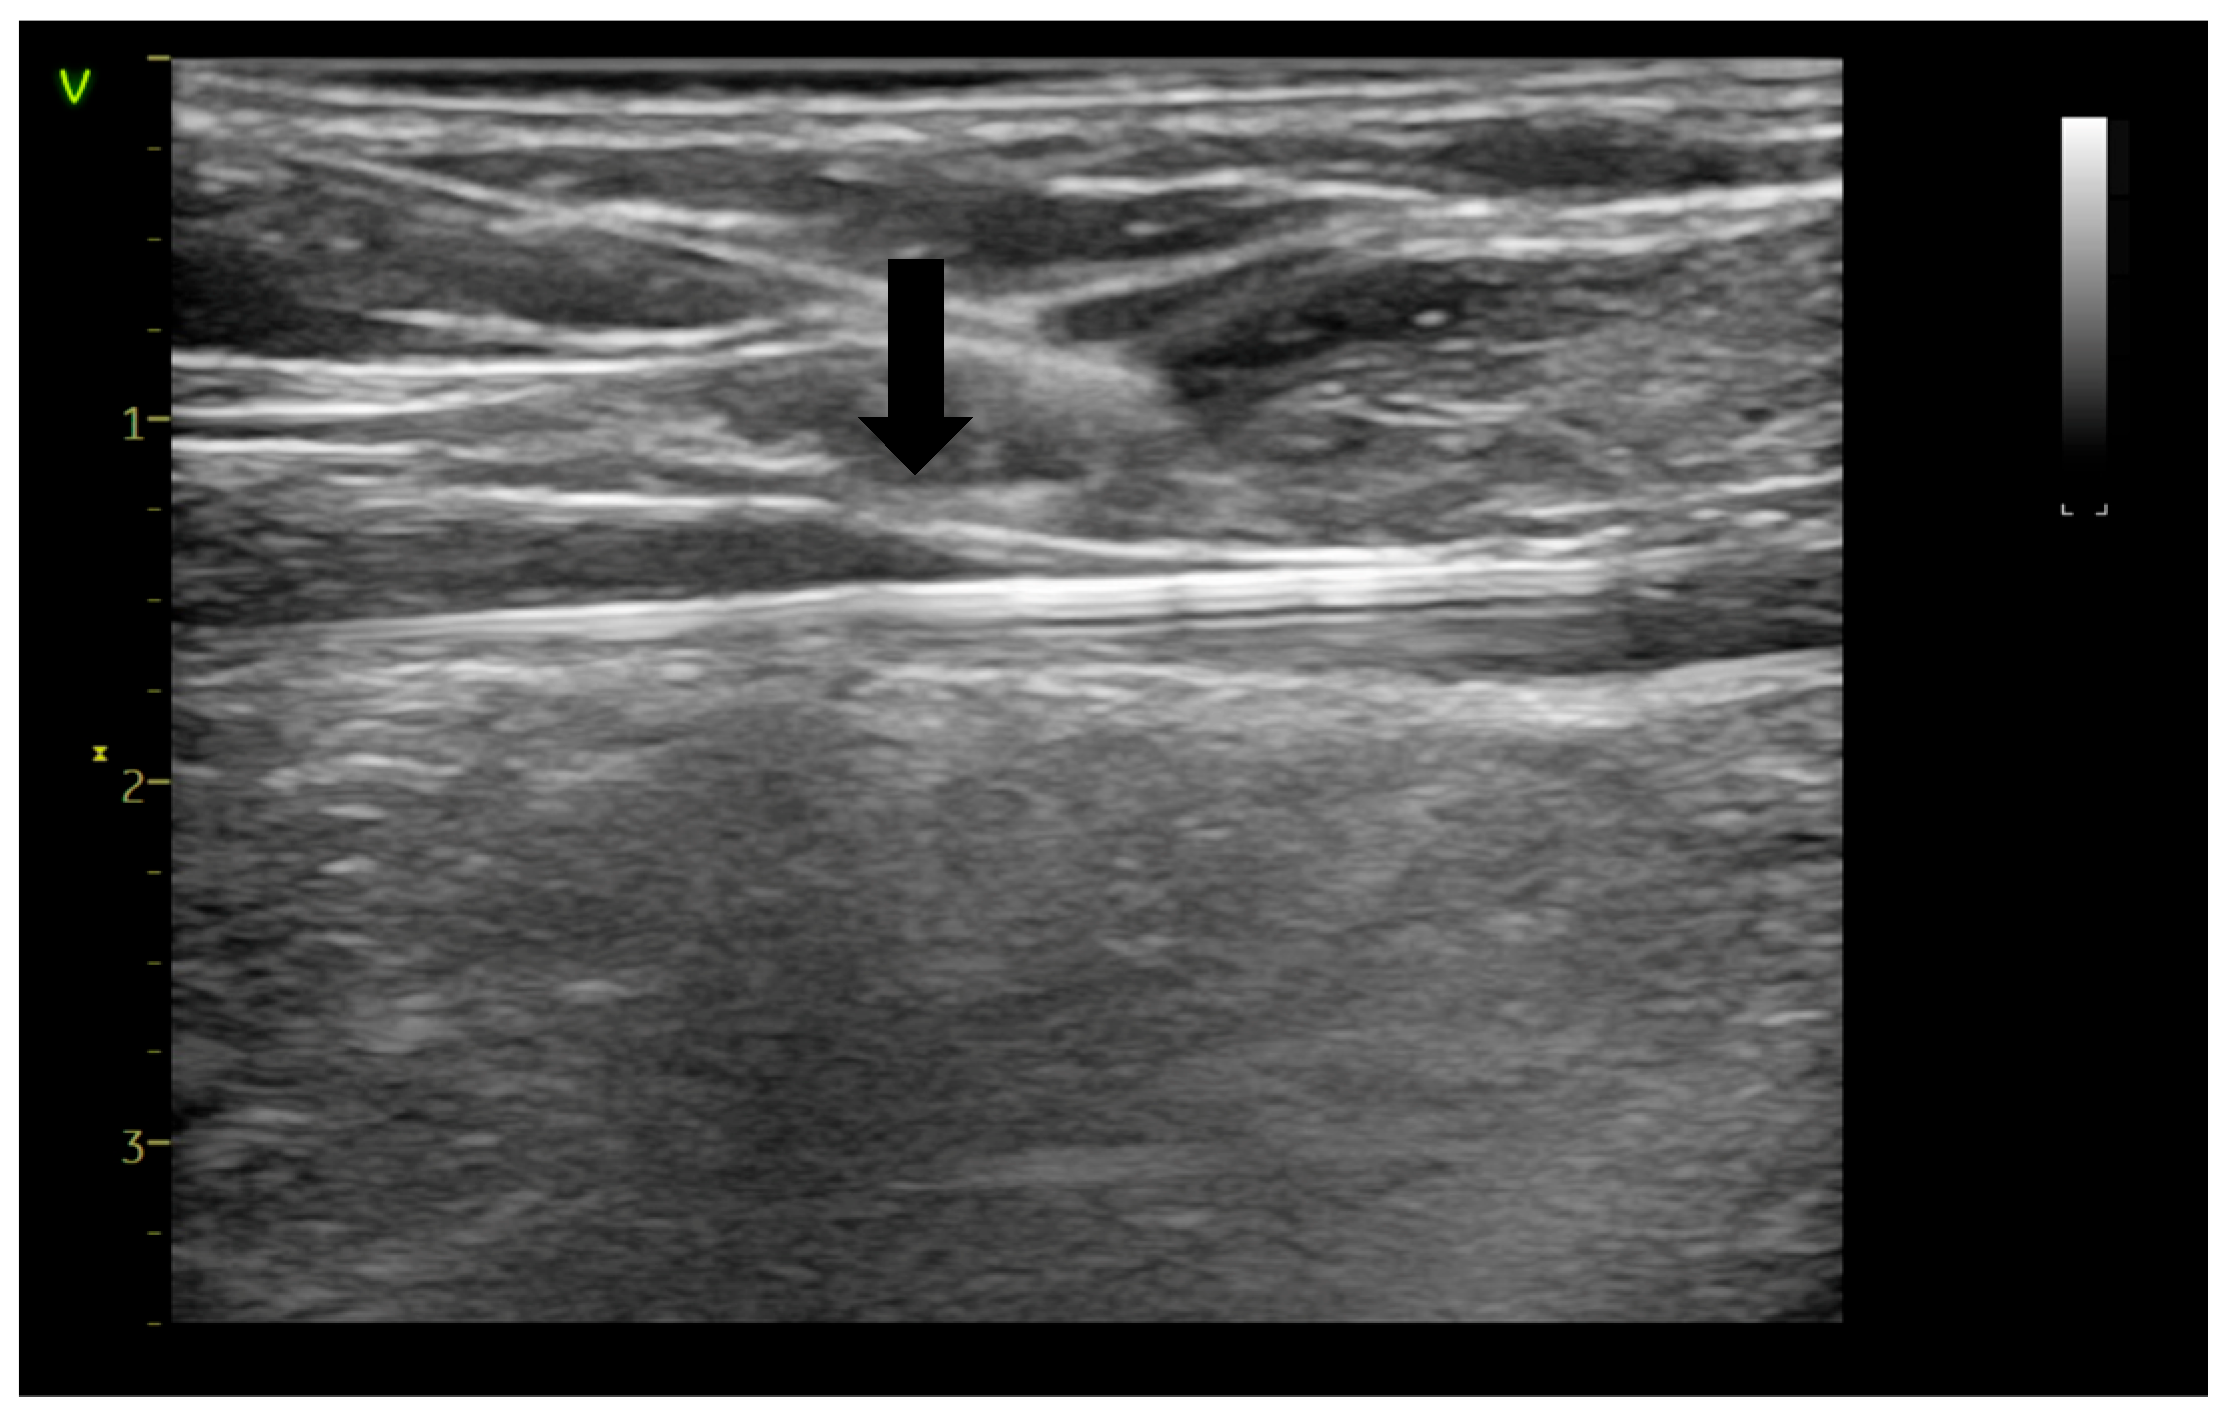

2. Materials and Methods